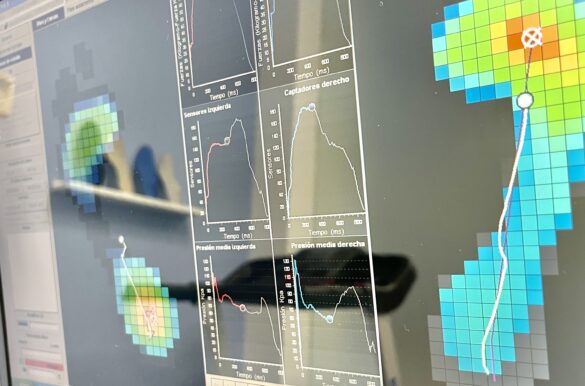

Beneficios del estudio de la pisada Prevención de lesiones y dolores crónicos. Alivio…

Un tratamiento a medida Las ortesis plantares no solo son un tratamiento correctivo…